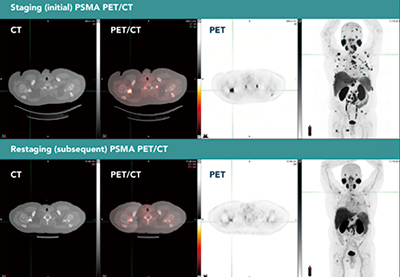

德国研究者Kniep等报告,在检测中危前列腺癌患者的淋巴结浸润情况时,所有术前影像学分期方法均有限。然而,前列腺特异性膜抗原(PSMA)-正电子发射断层扫描(PET)分期具有一定的预后价值。(BJU Int. 2026年1月23日在线版)

准确的淋巴结分期影响中危前列腺癌患者的预后和治疗选择。由于事件发生率低、敏感性不一以及对成本和辐射的担忧,关于计算机断层扫描(CT)、磁共振成像(MRI)和PSMA-PET的常规使用,各指南间存在冲突。因此,最佳分期策略仍不确定,这凸显了诊断准确性和肿瘤结局比较数据的必要性。

结果显示,25.8%(2079例)、5.0%(400例)和1.8%(148例)的患者分别接受腹部CT分期、PSMA-PET分期和腹部MRI分期。风险不良患者对比风险良好患者,CT分期(29.1% vs. 20.2%)和PSMA-PET分期(6.1% vs. 3.0%)的实施频率更高。

所有影像学分期在发现淋巴结浸润的敏感性方面均较低。PSMA PET分期的敏感性为13%(PPV为30.0%,NPV为89.5%),MRI的为8.3%(PPV为100%,NPV为92.5%),CT的为0.9%(PPV为22.2%,NPV为89.0%)。PSMA-PET相对较佳的分期性能表明,它可能识别出传统影像学未能检出的淋巴结病变子集。

PSMA-PET分期在肿瘤结局预测方面具有重要作用。术后60个月,PSMA PET阴性患者对比PSMA PET阳性患者的结局更好,无生化复发生存率分别为75.1%和45.4%,无转移生存率分别为95.5%和75.8%。